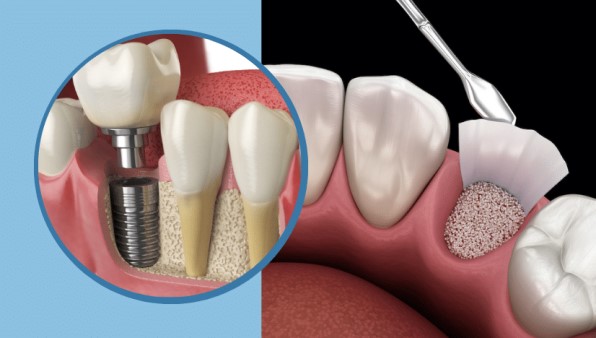

مراحل کاشت ایمپلنت دندان در ونک، ایمپلنت دندان یکی از پیشرفتهترین روشهای جایگزینی دندانهای از دست...

انواع روش های پیوند استخوان و مزایا و معایب هر کدام در کاشت ایمپلنت دندان در ونک. بازسازی استخوان یکی...

روکش ایمپلنت دندان در ونک آخرین مرحله...